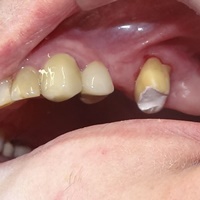

Dziesieć lat po wykonaniu mostu pacjent zgłosił się z recesją dziąsła i próchnicą korzenia. Zamiast ekstrakcji wykonano hemisekcję i nowy most.